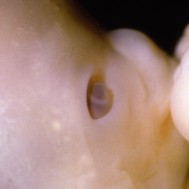

All essential body parts are present and accounted for. Your ankles have formed, your arms are long and bend at the elbows. With basic physiology in place, rapid growth and weight gain are the next steps![1]

You are intricately detailed, but still so tiny, only about 3/4 inch (20 millimeters) long.[2]